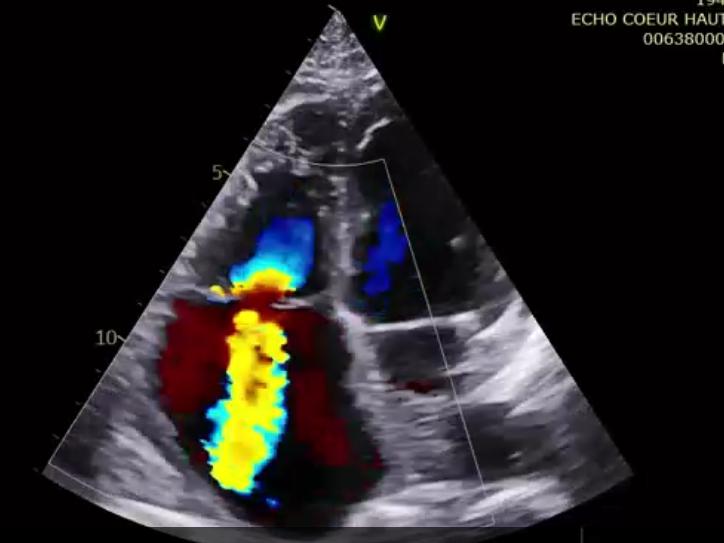

術前超聲提示大量三尖瓣反流